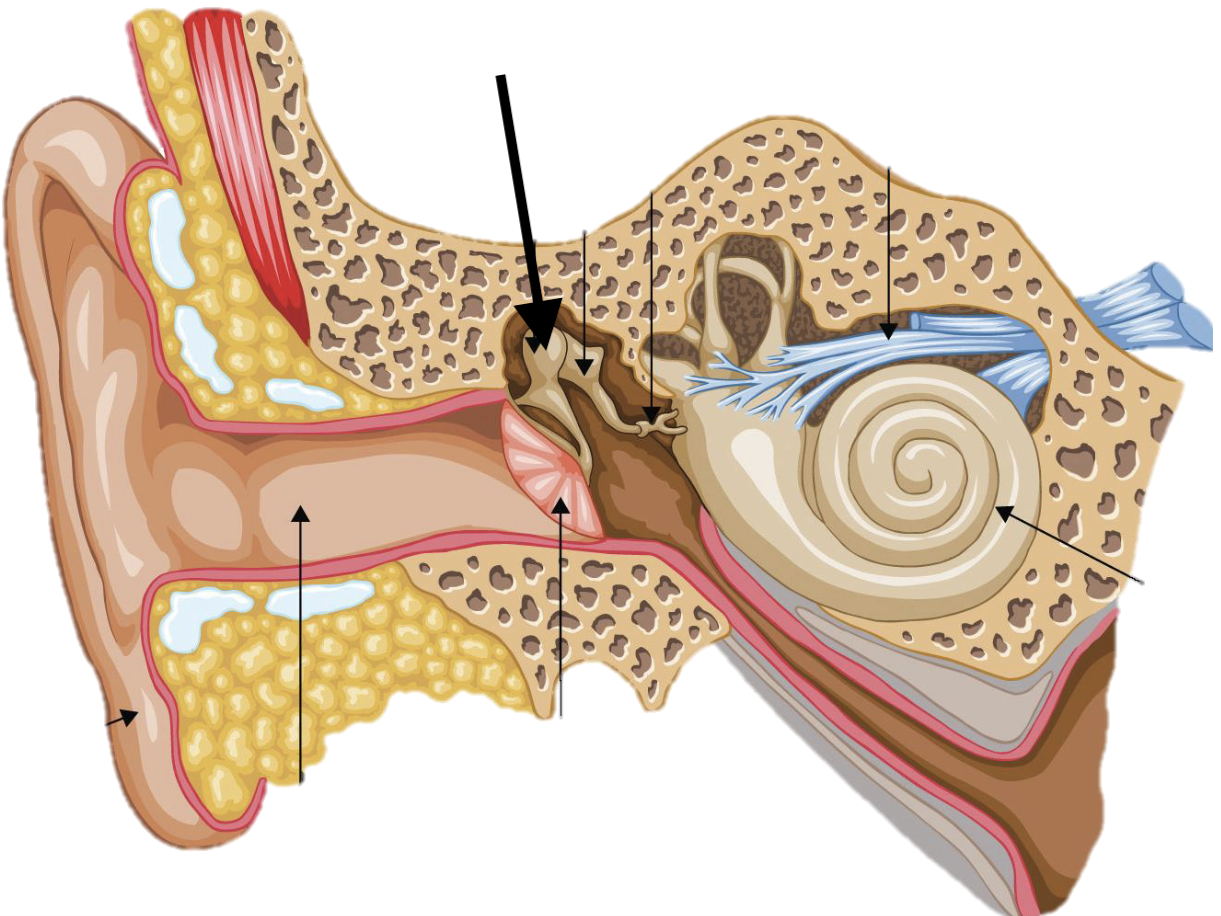

Name the feature of the ear ossicle

External acoustic meatus

Name the feature of the ear ossicle

Malleus

Name the feature of the ear ossicle

Incus

Name the feature of the ear ossicle

Stapes

Name the feature of the ear ossicle

Internal acoustic meatus

Name the feature of the ear ossicle

Cochlea

Name the feature of the ear ossicle

Temporal bone